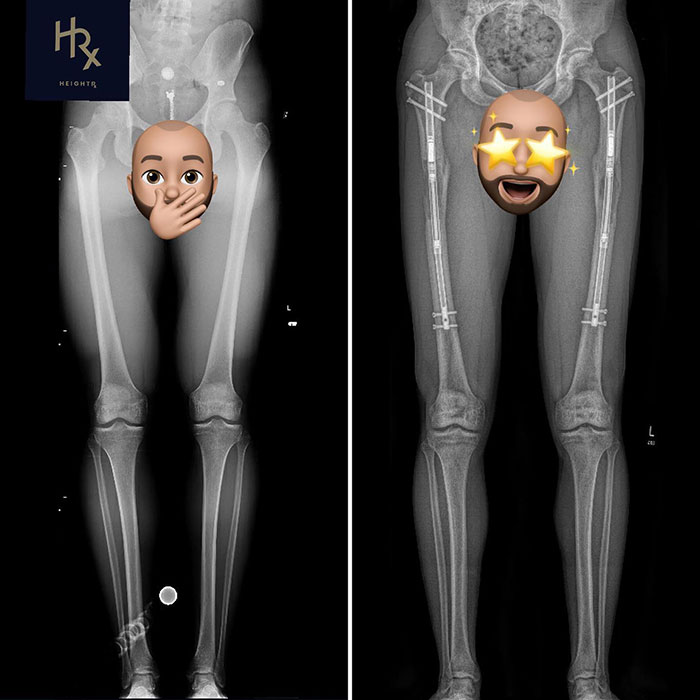

Theresia spent over €150,400 ($162,340) on procedures she underwent between 2016 to 2022, lengthening her height from 1.70 meters to 1.84 meters.

The German celeb spent years in surgery and recovery, having opted to increase the length of her legs by 14 centimeters, The Daily Mirror reported on April 11.

Theresia spent over €150,400 ($162,340) on procedures between 2016 to 2022, lengthening her height from 1.70 meters to 1.84 meters